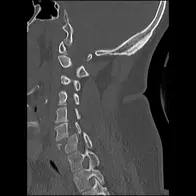

Rachis cervical